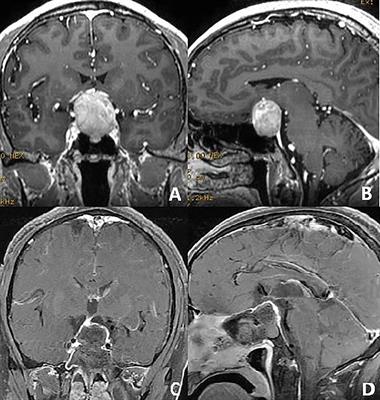

The Use of Micro Retractor in Endoscopic Endonasal Posterior Pseudocapsule Resection of Pituitary Macroadenoma. Technical Note